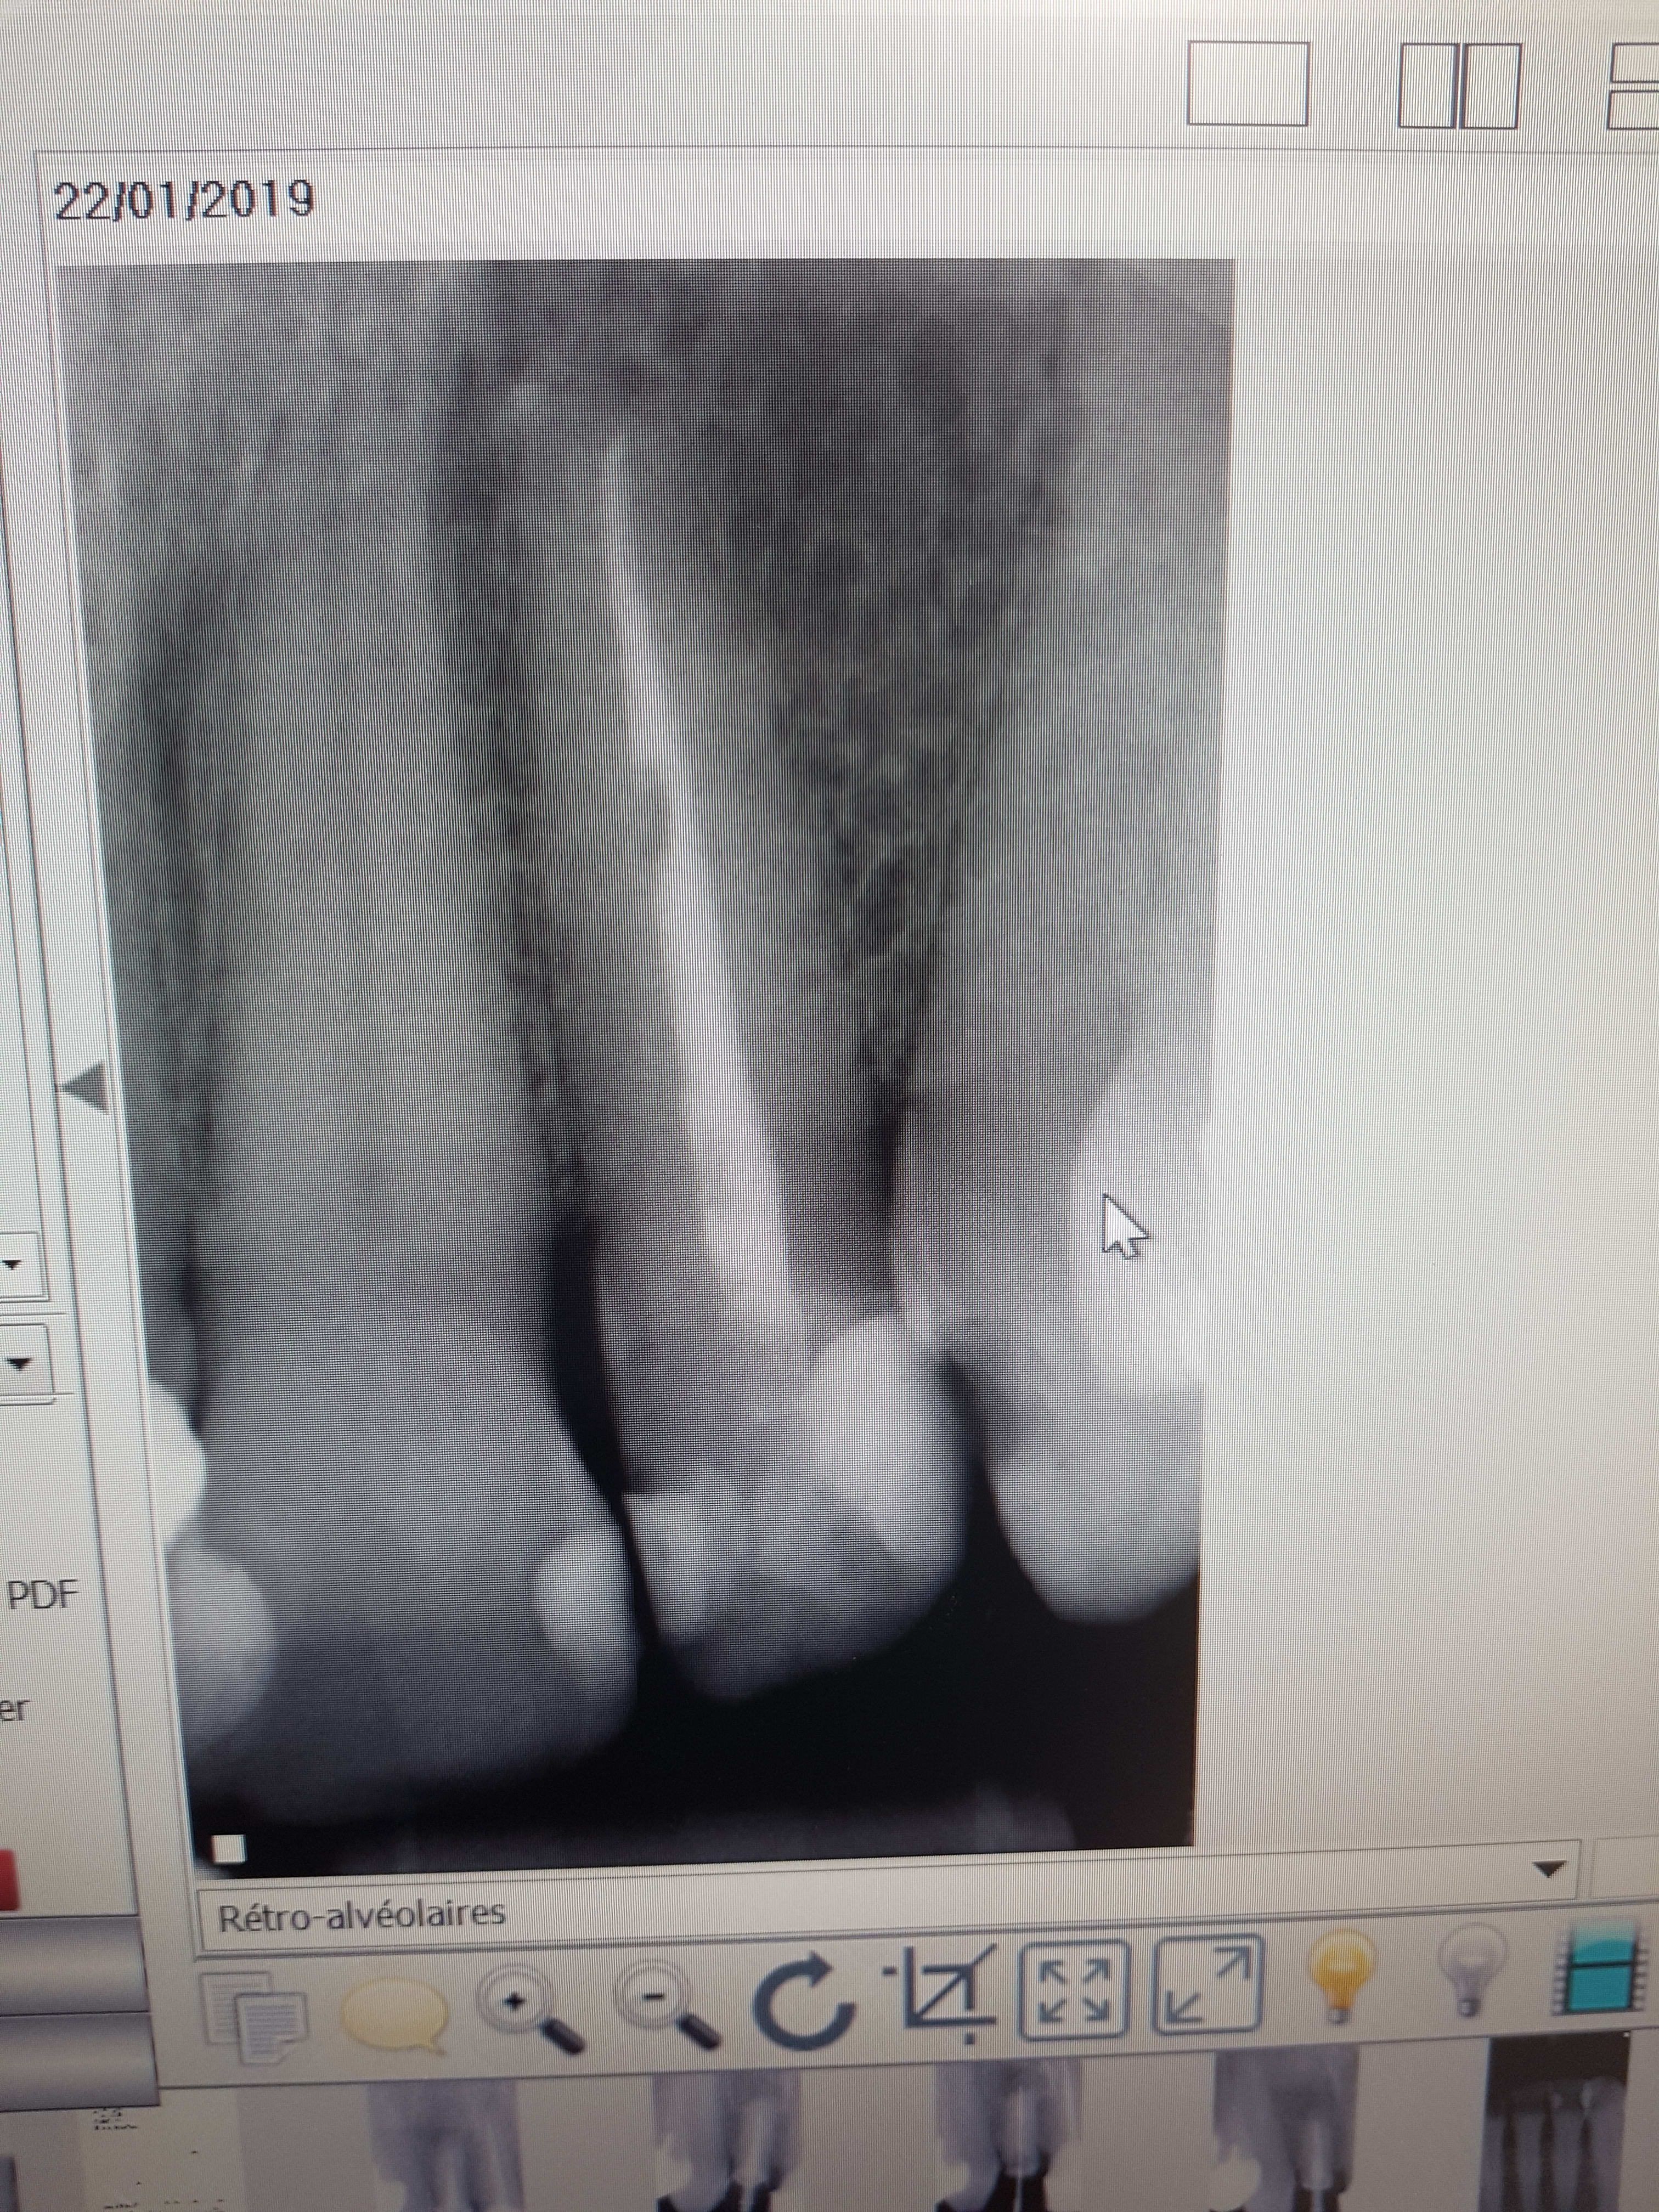

Patient de 50 ans, une 22 avec un grand compo vestibulo-disto-palatin fracturé, la partie mesio palatine toujours en place.

La dent est devitalisee (TC ancien ), et très colorée.